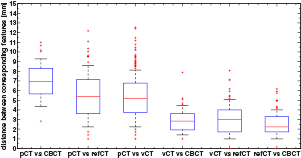

Figure 4 presents the results of the aSIFT evaluation for the 6 possible image inter-comparisons using Tz = 6 mm. We observed that the median distance between corresponding features was lowered when comparing the vCTCBCT, refCTCBCT and CBCTCBCT together, indicating that our registration algorithm yielded a vCTCBCT which agreed better with the CBCTCBCT/refCTCBCT than the pCTCBCT. The median distances are of the order of 2–3 mm, which is comparable to the planning CT resolution of 1.074 mm in the axial plane and 3 mm in the scan direction. Interpolating the CT to the CBCT coordinate system does not improve its resolution, however the fact that the phantom is homogenous in the Z direction means that for homogeneous parts of the phantom this interpolation should yield similar values as a higher resolution reconstruction. This is however not true at edges, where most features are detected. It is thus likely that our results are limited by a combination of the precision of the aSIFT algorithm and the slice thickness used. The median feature distances for the vCTCBCT versus refCTCBCT and pCTCBCT versus refCTCBCT comparisons are reported in table 3 before and after outlier removal. A Wilcoxon rank sum test between the feature distances of the vCTCBCT versus refCTCBCT and pCTCBCT versus refCTCBCT after outlier removal yielded p < 0.01. The aSIFT algorithm yielded matching features between the vCTCBCT and refCTCBCT/CBCTCBCT which exhibited large differences in their Z positions, hence the need for a Tz rejection. This is illustrated in figure 5 where accepted and rejected features are shown.

Figure 4. Boxplot of the distance between corresponding features for the 6 comparisons investigated after applying TZ = 6 mm. The horizontal line represents the median distance; the blue box represents the 25th and 75th percentiles and the whiskers extend to the most extreme data point not considered an outlier (plotted as red crosses). The median calculated here includes outliers, as opposed to table 3. Images were in the CBCT coordinate system.

Standard image High-resolution imageFigure 6 presents the results of the aSIFT evaluation between the pCTCBCT versus refCTCBCT and vCTCBCT versus refCTCBCT for all configurations. As expected configuration 3 shows the largest difference between pCTCBCT and vCTCBCT, however the vCTCBCT shows lower median feature distances than the pCTCBCT for configurations 1 and 2 as well.

Figure 6. Boxplot of the distance between corresponding features for the 3 configurations. The horizontal line represents the median distance; the blue box represents the 25th and 75th percentiles and the whiskers extend to the most extreme data point not considered an outlier (plotted as red crosses).